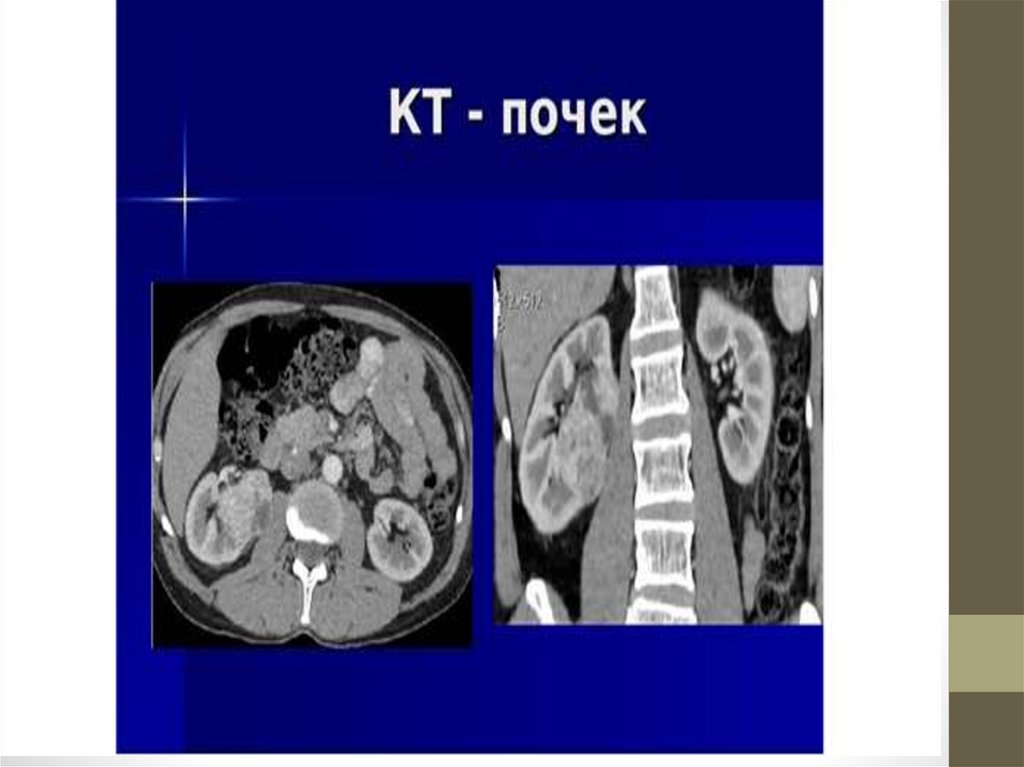

• Инструментальные: УЗИ, сканирование. КТ, МРТ,

ангиография почечных артерий.

• Функциональные методы исследования почекэкскреторная урография, моча по Зимницкому.